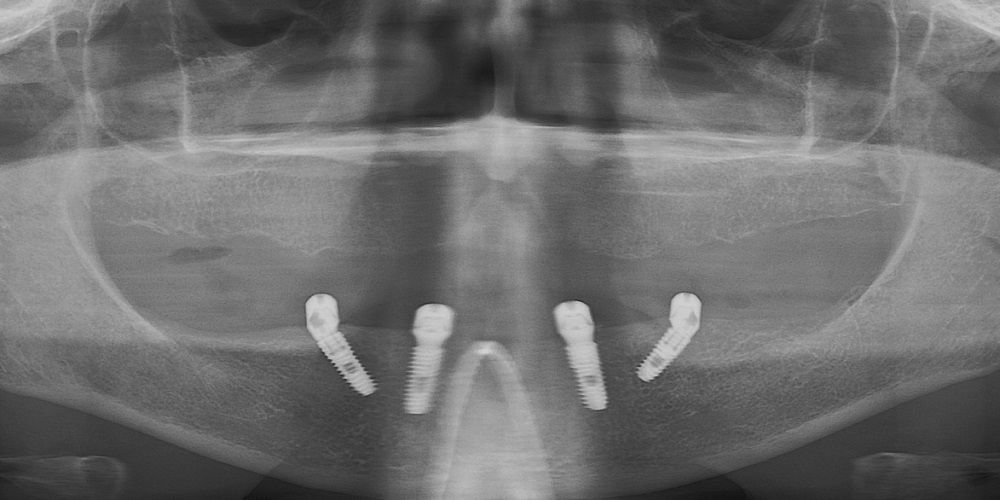

рентген имплантатоы

Имплантация жевательных зубов,

это самая востребованная операция.

Анна Анатольевна Кушнарева

хирург - имплантолог